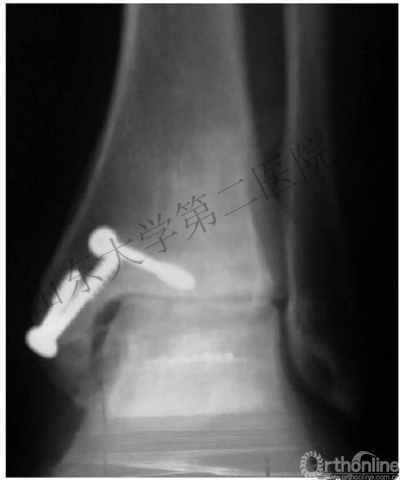

(2)下胫腓联合以两枚下胫腓螺钉固定。

*胫距关节面近端2-4cm,并且平行于关节面。

*水平面上从后向前有30°夹角。

*2枚螺钉or1枚?

有高位腓骨骨折时,打2枚螺钉;其他的打1枚螺钉。

(1)对于内踝骨折而三角韧带损伤的只需复位固定内踝骨折即可。

4.下胫腓联合需要用两枚下胫腓螺钉固定,除非可以确定下胫腓联合是否稳定。

5.在固定下胫腓联合的时候,需要恢复腓骨长度和旋转,将足放于中立位。